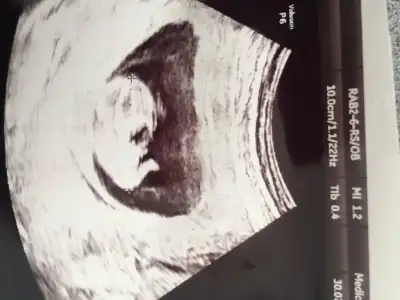

Kızlar benim kuzuya da bi yorum yapabilirmisiniz lütfen

Bide bunlar var bu arada zaman ayırıp yorum yaptığınız için teşekkürler

Bence kız bu minnoş çok dik degil paralelde degil pozisyonla alakalı değilse kız diyorum

şu 3. usg deki şeyin ne olduğunu merak ediyorum hala.. ayakları havaya dikip popoyu bize çevirdi poz verdi..

o görüntü geçen hafta videoda bariz ortada çıkıntı şeklinde idi -ki usg foto da bile çıktı anlamadım..

o yüzden kafam karıştı..

bu hafta ki görüntülemede önden (yani bebeğin karın kısmından bacak arası bakışı) baktı 10-15 sn arada bi çıkıntı gibi gbişi vardı ama henüz erken dedi..

bakalım kısmet hayırlısı ne ,1 ay sonra netleşecek..